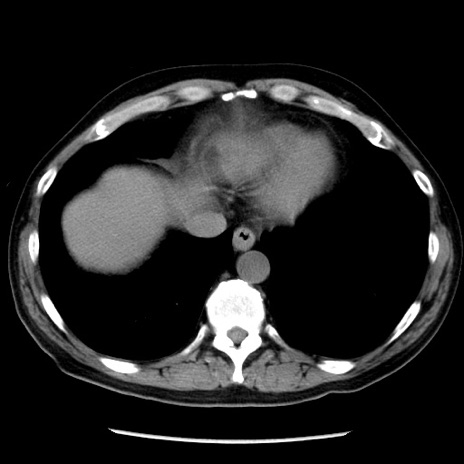

症例29(横断像)

【症例】40歳代男性

【現病歴】2日前から胃痛あり。徐々に周期的な激痛に変化した。本日になっても激痛があるため受診。

【身体所見】意識清明、BT 38-39℃台あり、腹部:膨満、やや硬、右下腹部に圧痛あり。

【データ】WBC 8500、CRP 23.26